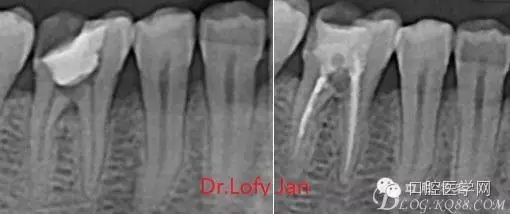

前言:自己做的一些曲面斷層片在未試尖根管治療中的病例整理,發(fā)現(xiàn)問題很多包括自身的,技術(shù)的,還有設(shè)備的問題,予以總結(jié)整理并期待進(jìn)一步提高。

根管治療術(shù)是牙體牙髓疾病治療中最復(fù)雜和最關(guān)鍵的治療項目。根管充填材料抵達(dá)根尖、并能嚴(yán)密堵塞根尖孔,是確保根管治療效果的關(guān)鍵指標(biāo)。為了保證根管充填到位,醫(yī)生需要在術(shù)前照牙片以了解牙根根管的數(shù)量、彎曲程度和長度,在術(shù)中有時需要插針照牙片來精確測量根管長度,術(shù)后必須照牙片以確定是否根管充填到位,如果欠填或超填,就需要重新充填、重新照牙片確認(rèn),直到根管充填到位。所以,在患者接受根管治療時有時會反復(fù)照牙片。

病例分析:曲面斷層片在x線輔助診斷與檢查中目前大多數(shù)文獻(xiàn)和著作都建議只能作為初診拍片檢查手段,不能作為終末疾病的確診與手術(shù)療效的評價指標(biāo),臨床大部分中小型門診都因為設(shè)備不齊全導(dǎo)致信息偏差很大。